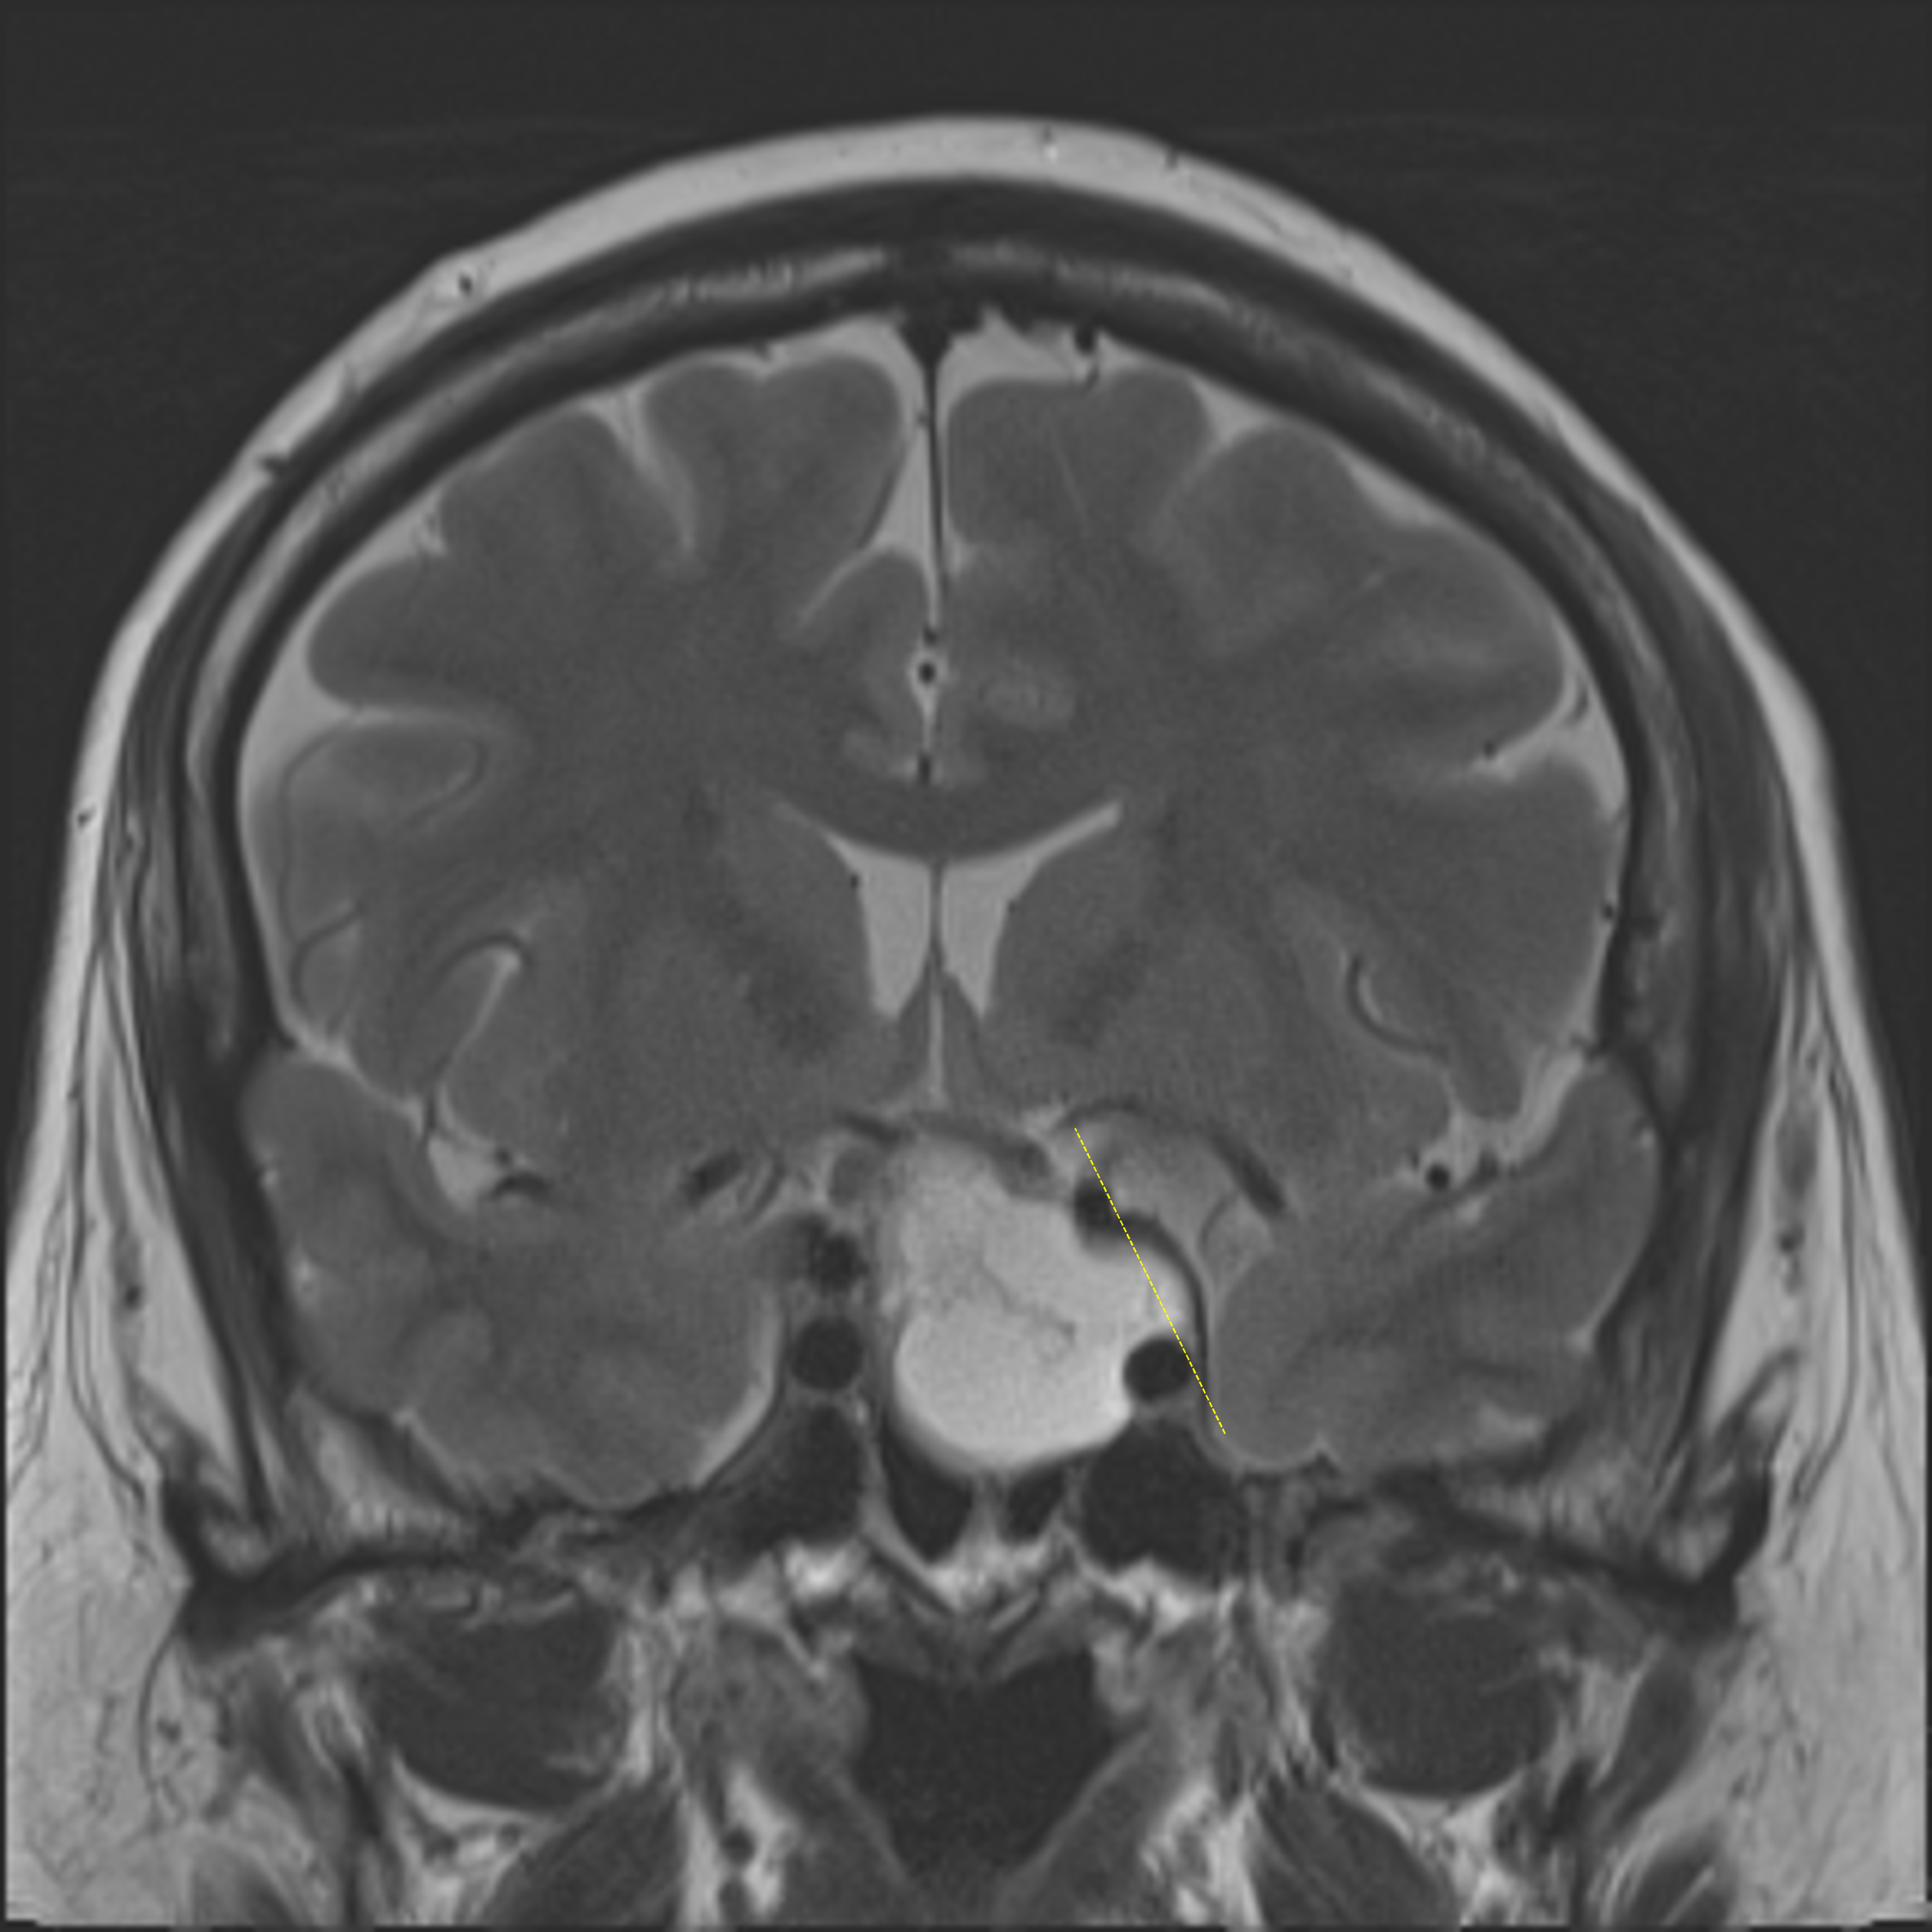

• The mass bulges lateral to the left lateral carotid tangent line, partially encasing the left cavernous internal carotid artery

Tumor bulges lateral to the left lateral carotid tangent line (yellow dotted line), suggesting cavernous sinus invasion.

Cystic pituitary macroadenoma